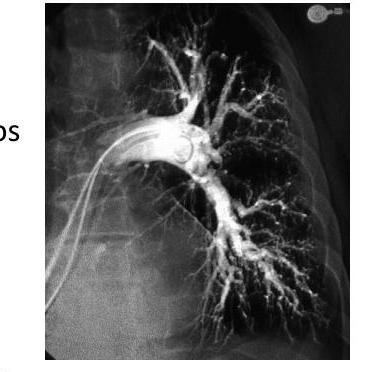

# ENFERMEDAD TROMOEMBÓLICA ## DEFINICIÓN El término trombosis se refiere a la formación de una masa anormal dentro del sistema vascular a partir de los componentes sanguíneos. La Enfermedad Tromboembólica Venosa (ETV) comprende un espectro de enfermedades que engloban la Trombosis Venosa Profunda (TVP) y de la Tromboembolia Pulmonar (TEP), ambos comparten los mismos factores predisponentes. La TVP es una oclusión de los vasos pulmonares debido a un coágulo sanguíneo, el 95% de los casos en el sistema venosos profundo de los miembros inferiores y posteriormente el émbolo se depoista en el área pulmonar. Cuando una TVP proximal no es tratada, ocurre una TP en el 33% de los casos y otro 33% presenta un embolismo subclínico. Otros orignees de émbolos son las venas pélvicas, las extremidades superiores y las cavidades cardíacas derechas.  # FISIOPATOLOGÍA El proceso de trombosis involucra diversos factores que predisponen a un individuo a sufrir de una oclusión trombótica que fueron descritos por Virchow desde el siglo XIX. ## TRÍADA DE VIRCHOW: - Lesión endotelial (Trauma, cirugía, fractura reciete, enveto previo de TVP) - Estasis o alteración del flujo sanguíneo (inmovilidad, obesidad, ICC, aumento PVC) - Estado hipercoagulable de la sangre (embaraza, postparto, ACO, cáncer, quemaduras severas) ## Triada de Virchow  Durante el episodio agudo se pueden apreciar las siguientes alteraciones fisiopatológicas: 1. Alteración del intercambio gaseoso: AUMENTO DEL ESPACIO MUERTO FISIOLÓGICO (zona que está siendo ventilada, pero no perfundida) por desequilibrio V/Q en el pulmón no obstruido (más perfusión que ventilación) y por shunt derecha a izquierda, que puede ocurrir a nivel intrapulmonar o intracardiaco. 2. Hiperventilación alveolar por estímulo refeljo nervioso. 3. Aumento de la resistencia dal flujo aérero por broncoconstricción de las vías aéreas distales al bronquio obstruido. 4. Disminución de la distensibilidad pulmonar por edema, hemorragia o pérdida de surfactante. 5. Aumento de la resistencia vascular pulmonar por obstrucción vascular o liberación de agnetes neurohumorales como la serotonina por las plaquetas. 6. Disfunción ventricular derecha. El fracaso ventricular derecho es la causa de muerte más habitual de la TEP. A medida que aumenta la resistencia vascular pulmonar, aumenta la tensión del VD, maor dilatación y disfunción ventricular. # EPIDEMIOLOGÍA - La ETV está ubicada en el 3o lugar como causa de muerte cardiovascular (después de enfermedad coronaria e isquemia cerebral) - Es un trastorno multifactorial, con incidencia anual de 1-2 por cada 1,000 personas - Más frecuente en hombres - Asociada a edad con incremento a 1 por cada 100 personas en mayores de 55 años. - Un 20 % de quien padece ETV no tiene factores de riesgo asociados. FACTORES DE RIESGO | RIESGO | ANTECEDENTE | | :--: | :--: | | ALTO | Fractura de cadera o miembros inferiores Cirugía ORTOPÉDICA Prótesis de cadera Cirugía mayor Poltirauma IAM Lesión de médula espinal | | MODERADO | Artroscopía Cateter central Quimioterapia Insuficiencia cardiaca congestiva Tratamiento hormonal Embarazo Trombofilia | | BAJO | Reposo en cama Inmovilidad Edad avanzada Laparoscopía Obesidad Venas varicosas Viajes en avión de largo recorrido Síndrome antifosfolípido Hiperhomocisteinemia Policitemia primaria EPOC | La resistencia a la proteína C activdada (Factor V de Leiden) es el estado de hipercoagulabilidad hereditario más frecuente en el TEP, seguido de las mutaciones del gen de la protrombina. Pero estos factores genéticos solo justifican 1/5 casos de TEP y la mayoría de los que tienen estos factores genéricos nunca desarrollan ETV. # CLÍNICA ## TVP DOLOR EN LA PANTORILLA: de inicio insidioso, que tiende a empeorar con el tiempo y se acompaña de palpación dolorosa - La TVP masiva es fácil de reconocer. El paciente presenta EDEMA DE MUSLO con palpación dolorosoa en zona inginal y sobre la vena femoral común. - La TVP de miembros superiores puede producir empastamiento de la fosa supraclavicular, aumento de diámetro del miembro o circulación colateral en la región anterior del tórax. ## TEP DISNEA: generalmente súbtia, es el síntoma más frecuente. Puede aparecer síncope o hipotensión brusca de causas no acalaradas. DOLOR PLEURÍTICO: aparece posterior a la disnea, siendo el segundo síntoma más frecuente. Taquicardia y Taquipnea: son signos constantes. Otros: hemoptsisis, opresión torácica, broncoespasmo | TEP Masivo | Se presenta con hipotensión o choque. Suele ser TEP de grana tamaño o difusos | | :--: | :-- | | TEP Moderado / Grande | Sin hipotensión ni choque Signos ecocardiográficos de sobrecarga de VD o elevación de marcadores de daño miocárdico | | TEP Moderado / Pequeño | Tensión arterial y función ventricular derecha normales. | # DIAGNÓTICO ## PROBABILIDAD CLÍNICA La estimación de la probabilidad clínica es el primer eslabón en la aproximación diagnóstica del TEP. El diagnóstico es difícil debido a lo inespecífico de la clínica. Lo primero que se debe hacer es terminar la probabilidad clínica, pues una probabilidad clínica baja de TVP o moderada/baja de TEP permiten descartar la enfermedad si el Dímero D es negativo sin utilizar otras pruebas de imagen. Dada la gravedad del proceso, un alto grado de sospecha clínica basta para iniciar anticoagulante. ## SISTEMA DE WELLS DE PROBABILIDAD CLÍNICA | Síntomas o signos de Trombosis Profunda | 3 | | :-- | :-- | | Diagnóstico alternativo menos probable | 3 | | FC >100 lpm | 1.5 | | Cirugía o inmovilización en las 4 semanas previas | 1.5 | | Episodio de tromboembolismo pulmonar o trombosis profunda previa | 1.5 | | Hemoptisis | 1 | | Cáncer | 1 | | PROBABILIDAD BAJA | 0-1 punto | | :--: | :--: | | PROBABILIDAD INTERMEDIA | 2-6 puntos | | PROBABILIDAD ALTA | >7 puntos | ## RADIOGRAFÍA Una placa normal o con escasas alteraciones aumenta la sospecha de TEP, aunque lo habitual es que existan anomalías: - Elevación del hemidiafragma - Atelectasias - Anomalías parenquimatosas pulmonares - Derrame pleural escaso y serohemático. SIGNO DE WESTERMARK: Oligohemia focal que produce hipertensión pulmonar. JOROBA DE HAMPTON: condensación parenquimatosa triangular de base pleural Asociado a TEP con infarto y presenta derra pleural de pequeña cuantía.  # ELECTROCARDIOGRAMA Las atleraciones más comunes - Taquicardia Sinusal y Anomalías Inespecíficas en el ST-T de V1 - V4. Puede haber signos de sobrecarga derecha como patrón SI,QIII,TIII (S en la derivación I, Q y T invertida en la II) ## LABORATORIO Marcadores Cardiacos: La elevación de Troponinas aumenta el riesgo de complicaciones y mortalidad en TEP estables. Gasometría: existe hipoxemia y aumento de gradiente alveoloarterial - Puede haber pacientes sin antecedentes de patología pulmonar con PO2 y D(a-a)O2 normales - La PaCO2 suele estar baja (hipoventilación refleja) - ALCALOSIS RESPIRATORIA. ## DÍMERO D Sensibilidad del 95% (85%-99%) y especificidad del 50% (29-71%) y un valor predictivo negativo del 95 al 100 %. Son generados por la acción del Factor VIII de coagulación sobre los monómeros y multímeros de fibrina Su elevación revela la presencia de fibrinólisis endógena, pero no es específico de TEP. Aumenta también en: IAM, neumonía, fallo derecho, carcinomas, cirugía, inmovilizaciones. Se debe determinar mediante ELISA Tiene un elevado valor predictivo negativo, especialmente si se combina con la probablidad clínca del Sistema Wells - Probabilidad Baja/Intermedia y Dímero D <500 \rightarrow se descarta TEP. No es muy util en pacientes con cáncer o cirugía reciente ya que la mayoría tiene >500 ng / ml ## TAC ESPIRAL CON CONTRASTE ## 1ra elección: ante la sospecha de TEP - Tiene sensibilidad mayor del 80 % y una especificdad mayor del 90 %. - Visualiza arterias del sexto orden - Tiene contraindicación la IR o alergia al contraste. Si el resultado es normal y la sospecha clínica es alta - ANGIOGRAFÍA PULMONAR. ## ANGIOGRAFÍA PULMONAR - Era el GOLD STANDARD hasta antes de la APTC. - Puede precisarse para el diagnóstico cuando hay una alta sospecha clínica y los otros estudios (TC Espiral, Ecografía) son negativos. - Se debe realizar en pacientes que se vayan a someter a algun tipo de intervención como una embolectomía o una trombolisis dirigida por cateter. # ANGIOGRAFÍA POR TOMOGRAFÍA La APTC Es la prueba que actualmente se considera GOLD ESTÁNDAR al ser menos invasiva. ## GAMMAGRAFÍA DE PERFUSIÓN PULMONAR  - Prueba de segunda línea, indicada en casos en los que no se pueda realizar la Tomografía. - Un resultado normal excluye el diagnóstico de TEP. - Un resultado anormal, se debe combinar con el de la gammagrafía de ventilación y así determinar la probabilidad gammagráfica de TEP.. - Una gammagrafía de alta probabilidad diagnóstia es la que presenta 2 o más defectos de perfusión segmentarios con gammagrafía de ventilación y radiografía de tórax normales. ## ECOCARDIOGRAFÍA - Baja sensibilidad para detectar TEP, puede ser util en casos de sospecha de TEP clínicamente graves, puesto que valora la función ventricular derecha y visualiza trombos importantes. - Se realiza transesofágico o transtorácico. ## ECOGRAFÍA VENOSA - Es la prueba no invasiva más utilizada en la actualidad para valorar TVP y ha llevado al desuso a la plestimografía y a la flebografía isotópica. - Es fiable en sintomáticos ambualtorios con sospecha de TVP; en sintomáticos y hospitalizados, pero la tasa de detección de TVP es mucho más baja. | TROMBO NO MASIVO | Presenta un excelente pronóstico y es la más frecuente. | | :--: | :-- | | TROMBO SUB-MASIVO | Presenta disfunción del ventrículo derecho del corazón pero con una presión arterial normal | | TROMBO MASIVO | Afectación de al menos la mitad de los vasos del pulmón. | # TRATAMIENTO El tratamiento primario consiste en la disolución del coágulo, ya sea mediante trombolisis o mediante embolectomía. La anticoagulación o el filtro de vena cava constituyen más bien una prevención secundaria a un nuevo episodio. - El tratamiento anticogulante es el factor más importante en la terpéutica de ETV. ## HEPARINAS ## HEPARINA NO FRACCIONADA (HNF) - Acelera la acción de la antitrombina III e inactiva el factora Xa, por lo que se previene la formación de un trombo adicional y permite que la fibrinolisis endógena disuelva algo del émbolo. - Requiere monitorizar TTPa, que debe duplicarse. - Su acción puede ser revertida con SULFATO DE PROTAMINA. - Se utiliza fundamentalmente en TEP con compromiso hemodinámico junto a los fibrinolíticos. ## HEPARINA DE BAJO PESO PESO MOLECULAR (HBPM) - Se administra por vía subcutánea. - Tiene una vida media plasmática más larga, ya que interactúa menos con las plaquetas y las proteínas. - Apenas se unen la antitrombina III y ejerce sy efecto fundamentalmente inactivando el factor Xa. - La monitorización del TTPa y el ajuste de dosis no suele ser necesaira, salvo en casos de obesidad, embarazo o IR grave. - En situaciones hemodinámicamente estables es tan eficaz y segura como la HNF. ## FONDOPARONUX Es un inhibidor selectivo del factor Xa que se administra por vía subcutánea una sola vez al día.no necesita controles de coagulación pero debe reducirse su dosis en IR. # ANTICOAGULANTES ORALES Inhibien la activación de los factores de coagulación dependientes vitamina K (II, VII, IX y X) ## Fármaco más utilizado - WARFARINA - Se administra desde el día siguiente del inicio de la heparina y se mantiene simultáneamente durante al menos 5 días. - El mantenimiento requiere de un INR entre 2-3 - Si el paciente está hemodinámicamente estable y adecuada función del Ventrículo derecho, los anticoagulantes son suficientes para buenos resultado. CONTRAINDICADOS EN EL EMBARAZO por teratogenia de los cumarínicos. El acenocumarol junto con la HNF se inicia hasta después de I parto, independientemente de la heparina utilizada. ## TROMBOLÍTICOS 1ra elección en TEP MASIVO (única indicación aprobada) y en la TVP Iliofemoral masiva o de cava inferior. - Debe realizarse de forma precoz, aunque puede haber respuesta hasta 2 semanas tras el TEP. - Objetivo: rápida lisis del trombo, aocrtando la fase de alto riesgo y reduciendo la mortalidad. - Fármacos empleados: Urocinasa, Estreptocinasa, Activador Tisular del Plasminógeno (rTPA). ## TRATAMIENTO INVASIVO Colocación de filtros en la cava inferior, embolectomía (si hay compromiso hemodinámico grave que no responde a fibrinolíticos) o la tromboendareterectomía (en los casos de hipertensión pulmonar crónica secundaria a TEP con clínica grave) ## Indicaciones del filtro en cava inferior: - Contraindicaciones o complciaciones de anticoagulación en pacientes con ETV o alto riesgo de la misma. - TEP recurrente pese a anticoagulación - Gran trombo flotante en vena cava inferior - Realización simultánea de embolectomía o tromboendarterectomía - Profilaxis en riesgo extremo. Los fltros evitan TEP en la fase aguda pero a largo plazo aumentan el riesgo de TVP, por lo que los pacientes que lo usen, deben permanecer anticoagulados. ## DURACIÓN DE ANTICOAGUALNTES Se recomienda 3 - 6 meses cuando es el primer episodio en pacientes con factores de riesgo reversibles. En caso contrario, mantenerlo indefinidamente, valorando periodicamente si el riesgo de sangrado supera al beneficio de la anticoagulación.  # DIGNÓSTICO TEP  (c) Copyright 2021-2022 Joyas ENARM - Todos los derechos reservados -